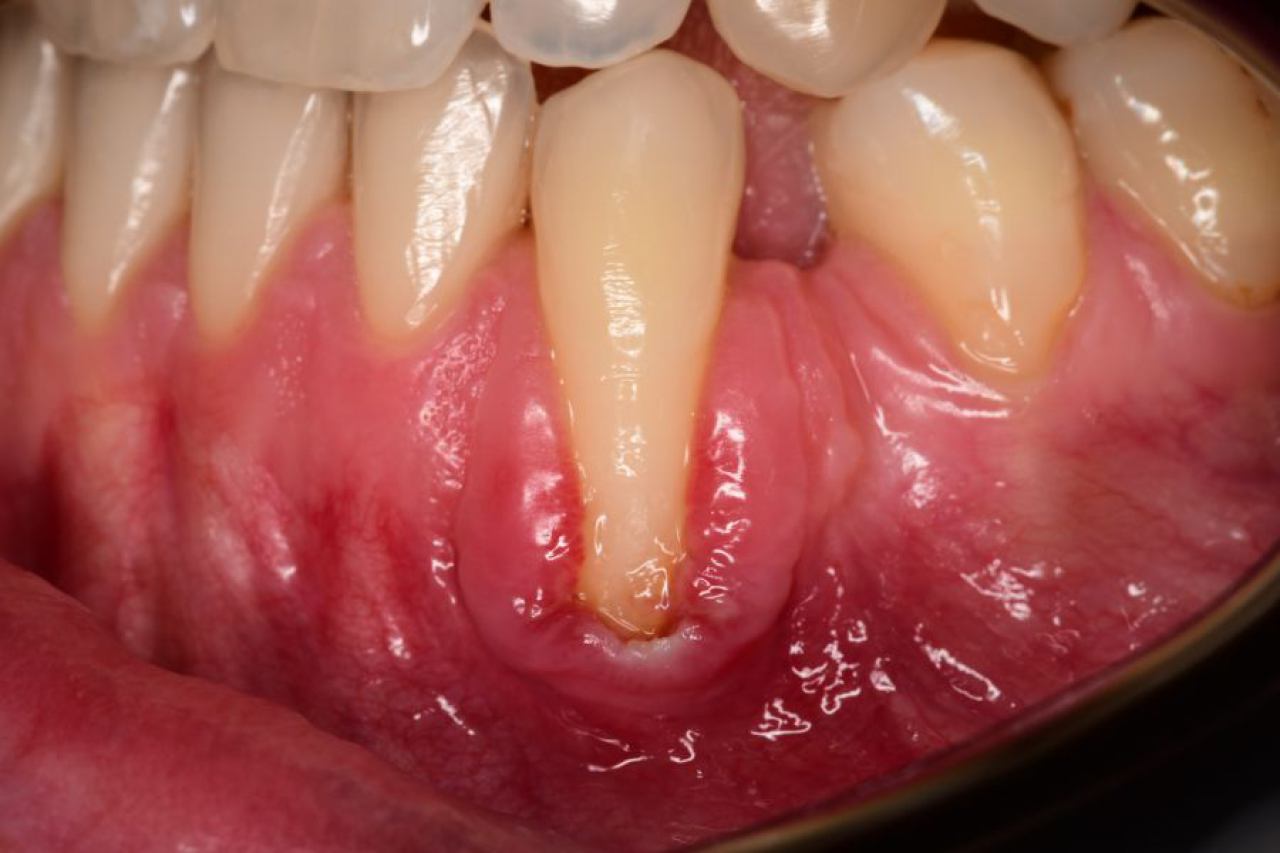

Regeneracija kosti i mekog tkiva

Gingivalne recesije u narodu poznatije kao „povlačenje zubnog mesa" moguće je korigirati kirurškim zahvatom te vratiti gingivu (zubno meso) u fiziološki položaj mikrokirurškim tehnikama. Zahvati koje odrađujemo kod regeneracije kosti i mekog tkiva su podizanje dna sinusa (sinus lift) i nadomještanje izgubljenog volumena kosti (augmentacija kosti, regeneracija kosti).